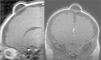

La resonancia magnética (RM) mostró la existencia de un proceso expansivo quístico (fig. 1), cuyo contenido mostraba una intensidad de señal similar a la del líquido cefalorraquídeo, situado en la fontanela anterior. Estaba recubierto por el cuero cabelludo, sin que existiera dehiscencia de la sutura. Tras la inyección de contraste paramagnético, la citada lesión no presentó captación del mismo (fig. 2).